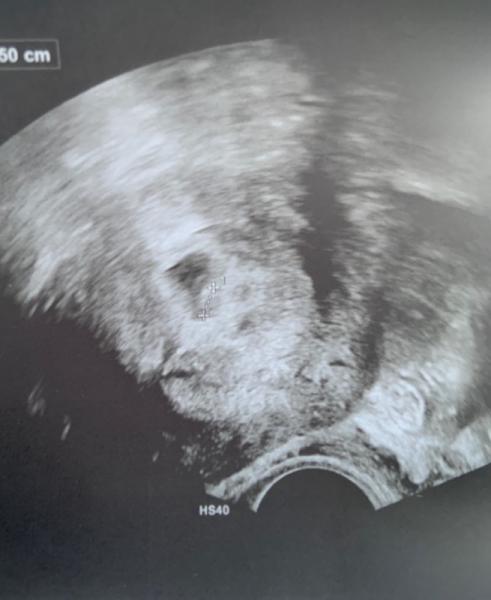

Ich wollte euch ja ein Update geben. Man sah zwar mehr in der Fruchthöhle aber noch nichts ganz genaues. Nun war meine Ärztin eher unsicher und wollte HCG messen. Am Montag dann nochmal. Bin ab morgen erst 7. SSW und hoffe es liegt nur am frühen Zeitpunkt.. naja muss man eben abwarten. Bin hin und hergerissen.

Bild zu Update.. wieder am zittern.. - Forum für Juli - Mamis

Ja das stimmt ich versuche positiv zu bleiben. Immerhin sieht man ja doch einiges im Bild denke ich. Daher bin ich guter Dinge.

Dankeschön.. er war ja eigentlich schon da, sieht man auch auf dem Bild aber der Ärztin ist das noch zu wenig.. undeutlich